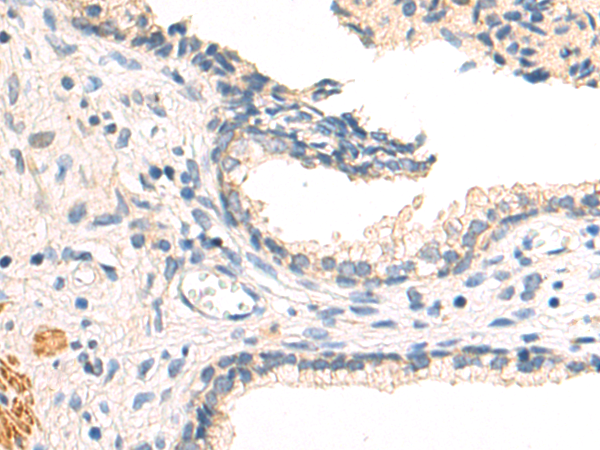

分类: 科研抗体货号: P07712别名: NR1I1; PPP1R163应用: IHC反应种属: Human, Mouse, Rat